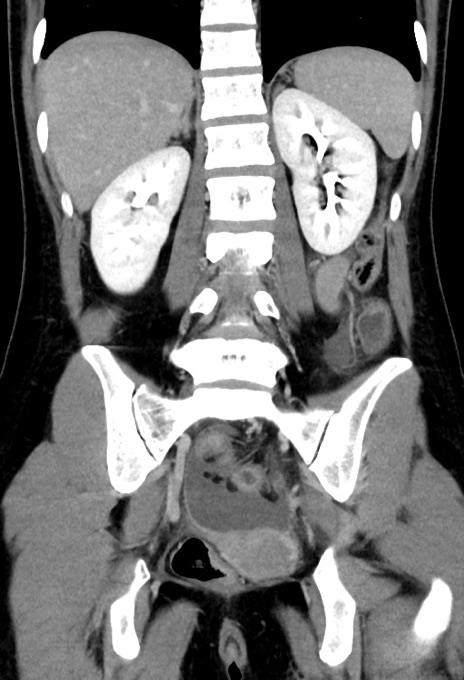

症例17(冠状断像)

【症例】20歳代女性

【主訴】嘔吐、下腹部痛

【現病歴】昨日夕食後に嘔吐し下腹部痛が出現。本日になっても嘔吐持続し改善しないため来院。

【身体所見】意識清明、BT 37.2℃、BP 108/67mmHg、腹部:平坦、やや硬、下腹部正中から右にかけて圧痛あり、反跳痛軽度あり、tapping pain(+)。

【データ】WBC 13600、CRP 14.94